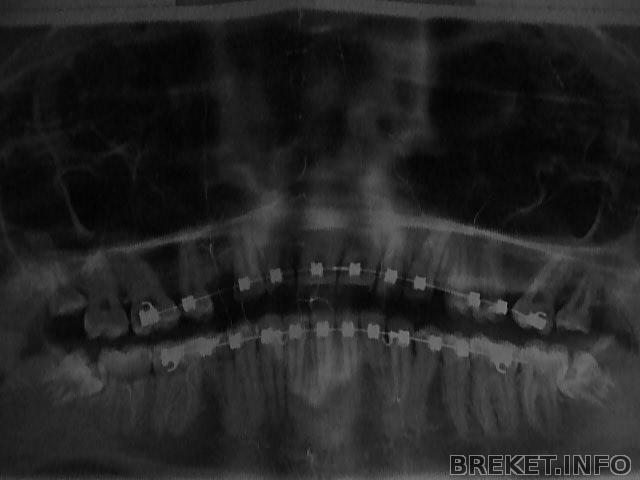

Люди ,мне ортодонт сказал их не удалять ...А хирург которая удаляла четвёрки советовала бы их всех удалить, так как наверху растут прям в щёку .. А внизу они вообще непонятно в каком положении... Верхние почти довылезли, а нижние .. один только прорезался и видно что он торчит непонятно каким своим углом... Я боюсь что нижние восьмёрки испоганят нижнюю челюсть, дело в том что где восьмёрка вылезла уже немного внизу стянулся сразу промежуток между 3 и 5 .. а сдругой стороны не вылезла и промежуток присутствует... А тяги внизу с двух сторон между 3 и 5... Ваше мнение очень интересно .. Вот снимок http://breket.info/images/image1073772900

Так почему орта не говорит удалять.. Я прсото боюсь эти восьмёрки удалять, тут нассмотрелась кому рты рвут , у кого потмо щёки хомяка и синяки на пол щеки и шеи.... А так результат мой уже кое какой я не хочу портить ни в коем случае...В договоре даже прописано , что за рецидив вызванный зубами мудрости клиника ответственности не несёт .. Удивляюсь ,конечно, ортше..

Хм... Странно, на снимке отчетливо видно, что нижние восьмерки подпирают семерки...

На снимке, по мне так, все очевидно. Нижние подпирают зубной ряд, это ничем хорошим не кончится. Я бы не стала рисковать результатом и удалила бы все от греха подальше. Вылезти они все равно нормально не смогут, зато запросто испортить могут то, к чему Вы так долго шли.